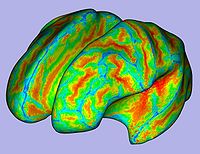

- 1.5. Cortical thickness computation

- Asymmetric cortical thickness on label map

- Tool: CortThick (UNC Slicer3 external module)

- 1.8. Cortical thickness attribute computation

- Cortical thickness interpolation on genus-zero surface

- 1.9. Sulcal depth computation

- Sulcal depth computation using genus-zero surface and inflated one

- 1.11. Surface area computation

- Local surface area measurement on smoothed genus-zero surface